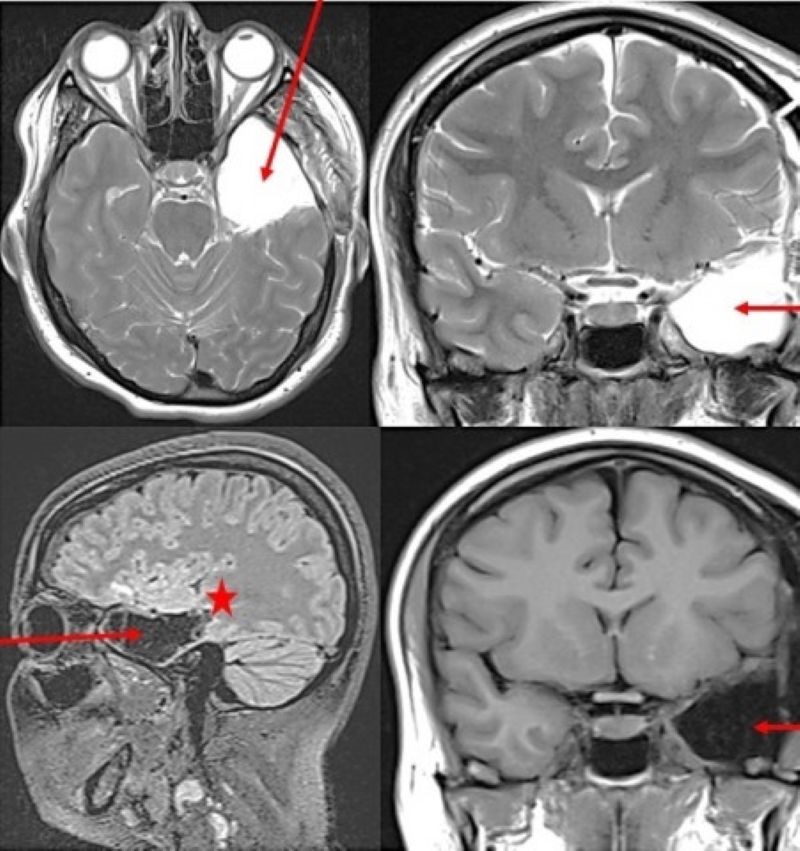

С 15 лет девушка страдала тяжелой формой эпилепсии, не поддающейся медикаментозной коррекции. Приступы могли повторяться до 6-8 раз в день, сопровождаясь головной болью, судорогами и потерей сознания. Девушку направили в стационар ККБ.

Врачи решили удалить девушке часть левой височной доли и гиппокамп, используя метод awake-хирургии — вмешательства с пробуждением. Все дело в том, что у правшей в этой части мозга расположен центр речи, который могут случайно повредить во время операции.